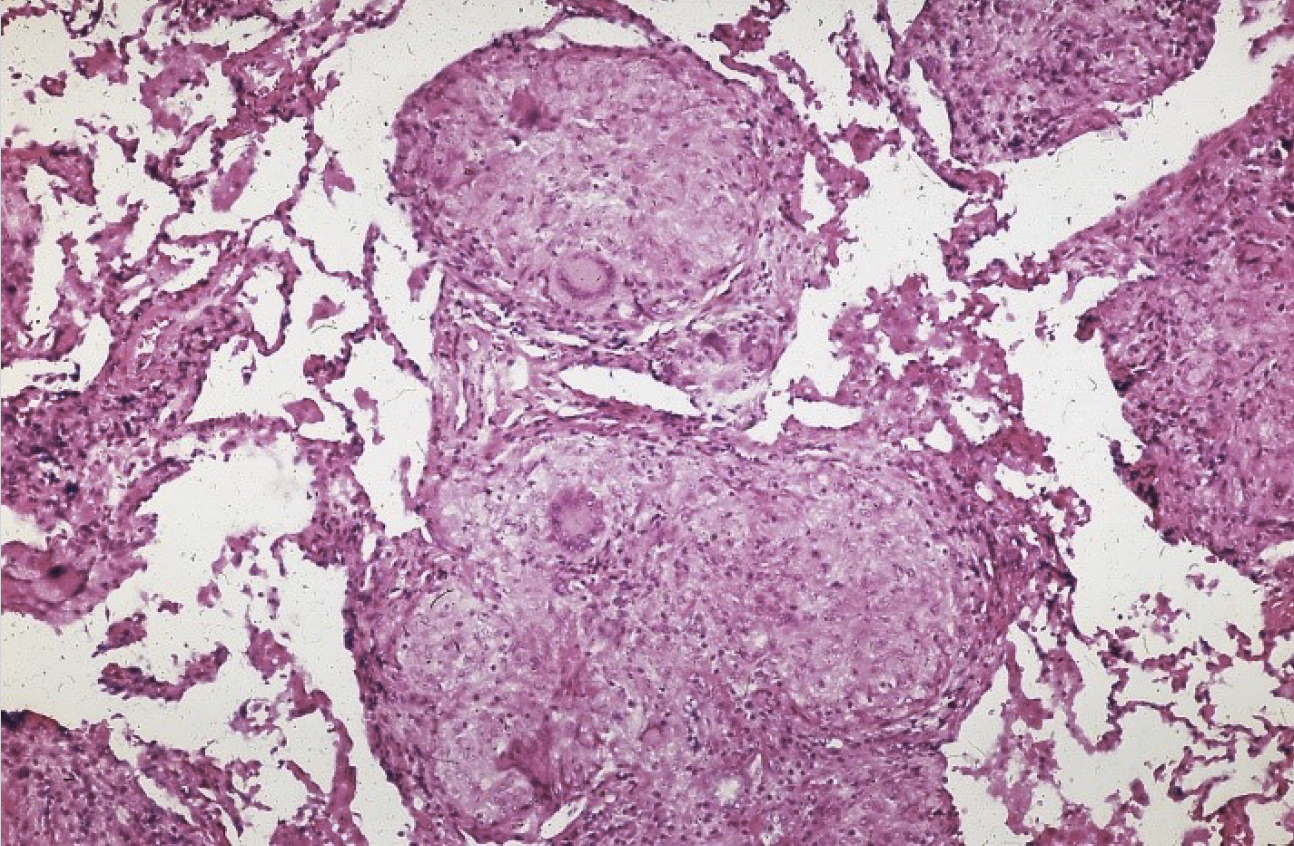

Mann, 28 år, dataingeniør. Tidligere frisk, ingen medisiner. Relativt akutt syk med feber, influensalignende symptoler, tørrhoste, smerter i ledd. Fikk etter hvert ømme, røde flekker på leggene. Røntgen thorax viste forstørrede lymfeknuter i hilus. Som ledd i utredningen ble det gjort bronkoskopi med biopsier.

Hva er den mest sannsynlige diagnosen?